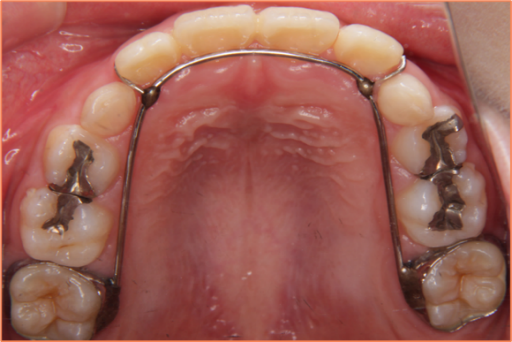

保定装置

治療期間:2年以上

装置料:なし(動的治療時に使用した装置料に含まれます。)

一期治療での目標達成後は、後戻り(歯が元の位置にもどろうとすること)を防止し、残っている乳歯が永久歯へスムーズに交換できるようにするために、保定装置を使用する必要があります。お口の状態によって使用する装置は異なり、矯正歯科医がベストな装置を決めていきます(基本的に患者様がご選択することはできません)。

子どもの場合、すべての歯が永久歯に生え変わり、成長がある程度落ち着いてくるまでは保定装置の使用が必要です。すべての歯が永久歯に生え変わるのが12~14歳頃となり、男の子だと高校生くらいまで成長が続くことがあります。この時期までは、数か月~1年おきの定期的な観察が必要になります。